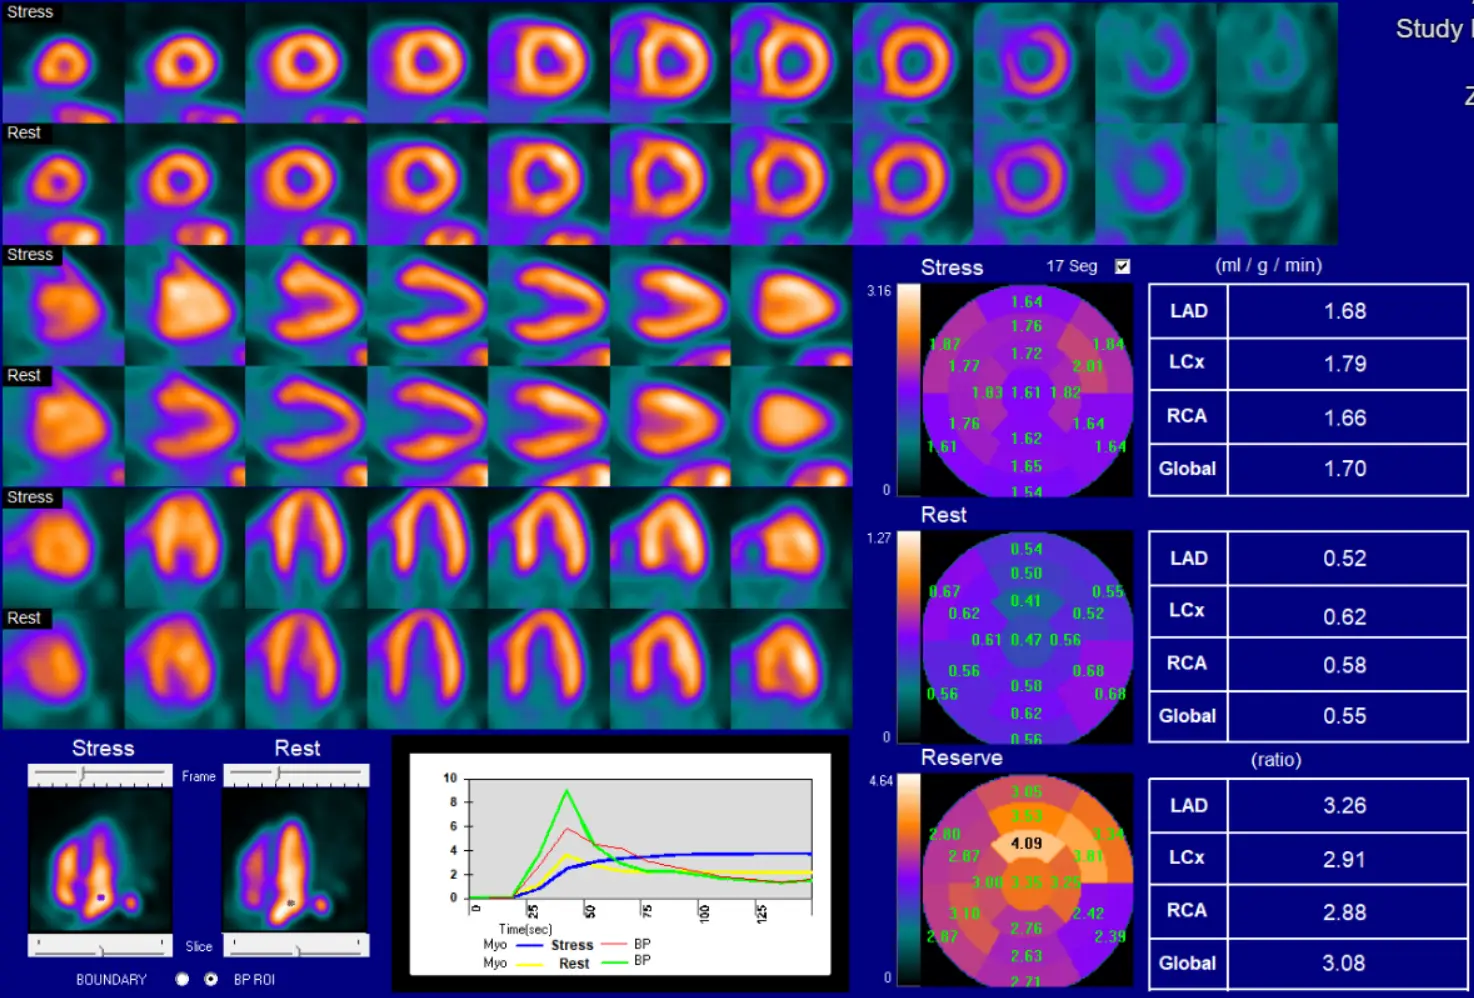

Reporting Flows

- Post-CABG you divide circulation between native and graft circulation. In the native circulation, physiology rapidly deteriorates (→ low flow). So we will typically see greater amounts of calcification in native circulation and low flow. This is not a reflection of graft closure, rather it is progression of native disease post-CABG.

- ⚠️ Be careful about reporting flows post-CABG so that referring doctor is not concerned about low flows and inadvertently sending patient to cath lab. If normal, Bateman will report them. If not normal (especially globally), it is probably best to not report them.

- ‘Not reported because not clinically relevant.’

- Other conditions where reporting flows may not be clinically relevant would be liver failure, renal failure.

- In the plateau phase, the signal-to-noise reflects the counts in myocardium (blue) and blood pool (red)

- Resting flows can be documented as high if the graph starts at is above 0.

- Generally peak rest blood pool (green) is 30% higher than peak stress blood pool (red).

- If < 30%, then potentially problematic for flow calculation

- You should expect a sharp rise and fall for the blood pool curves before the plateau phase. If it is wide, then there may be a technical issue.

- Compartment models are more sensitive if the QC is problematic.

Below is an example of impaired quality due to a technical issue, such as poor IV affecting infusion, long IV tubing, etc.